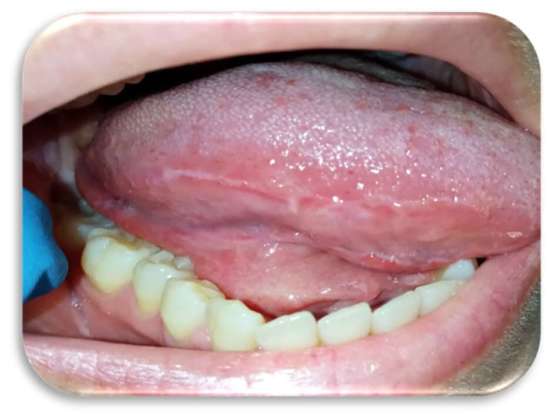

Sia sui margini linguali che sulle mucose geniene erano presenti, inoltre, segni di morsicatio buccarum e linea alba (Figure 3 e 4).

Al quarto giorno di applicazione, la paziente riportava un notevole miglioramento sintomatologico. A sette giorni c’era stata una regressione completa delle lesioni (Figure 5-6), con mucosa integra e normocromatica dove residuava linea alba a livello genieno e linguale (Figure 7-8), per la quale era stato consigliato alla paziente l’uso di un bite inferiore in resina morbida per evitare ulteriori traumi ai tessuti molli.